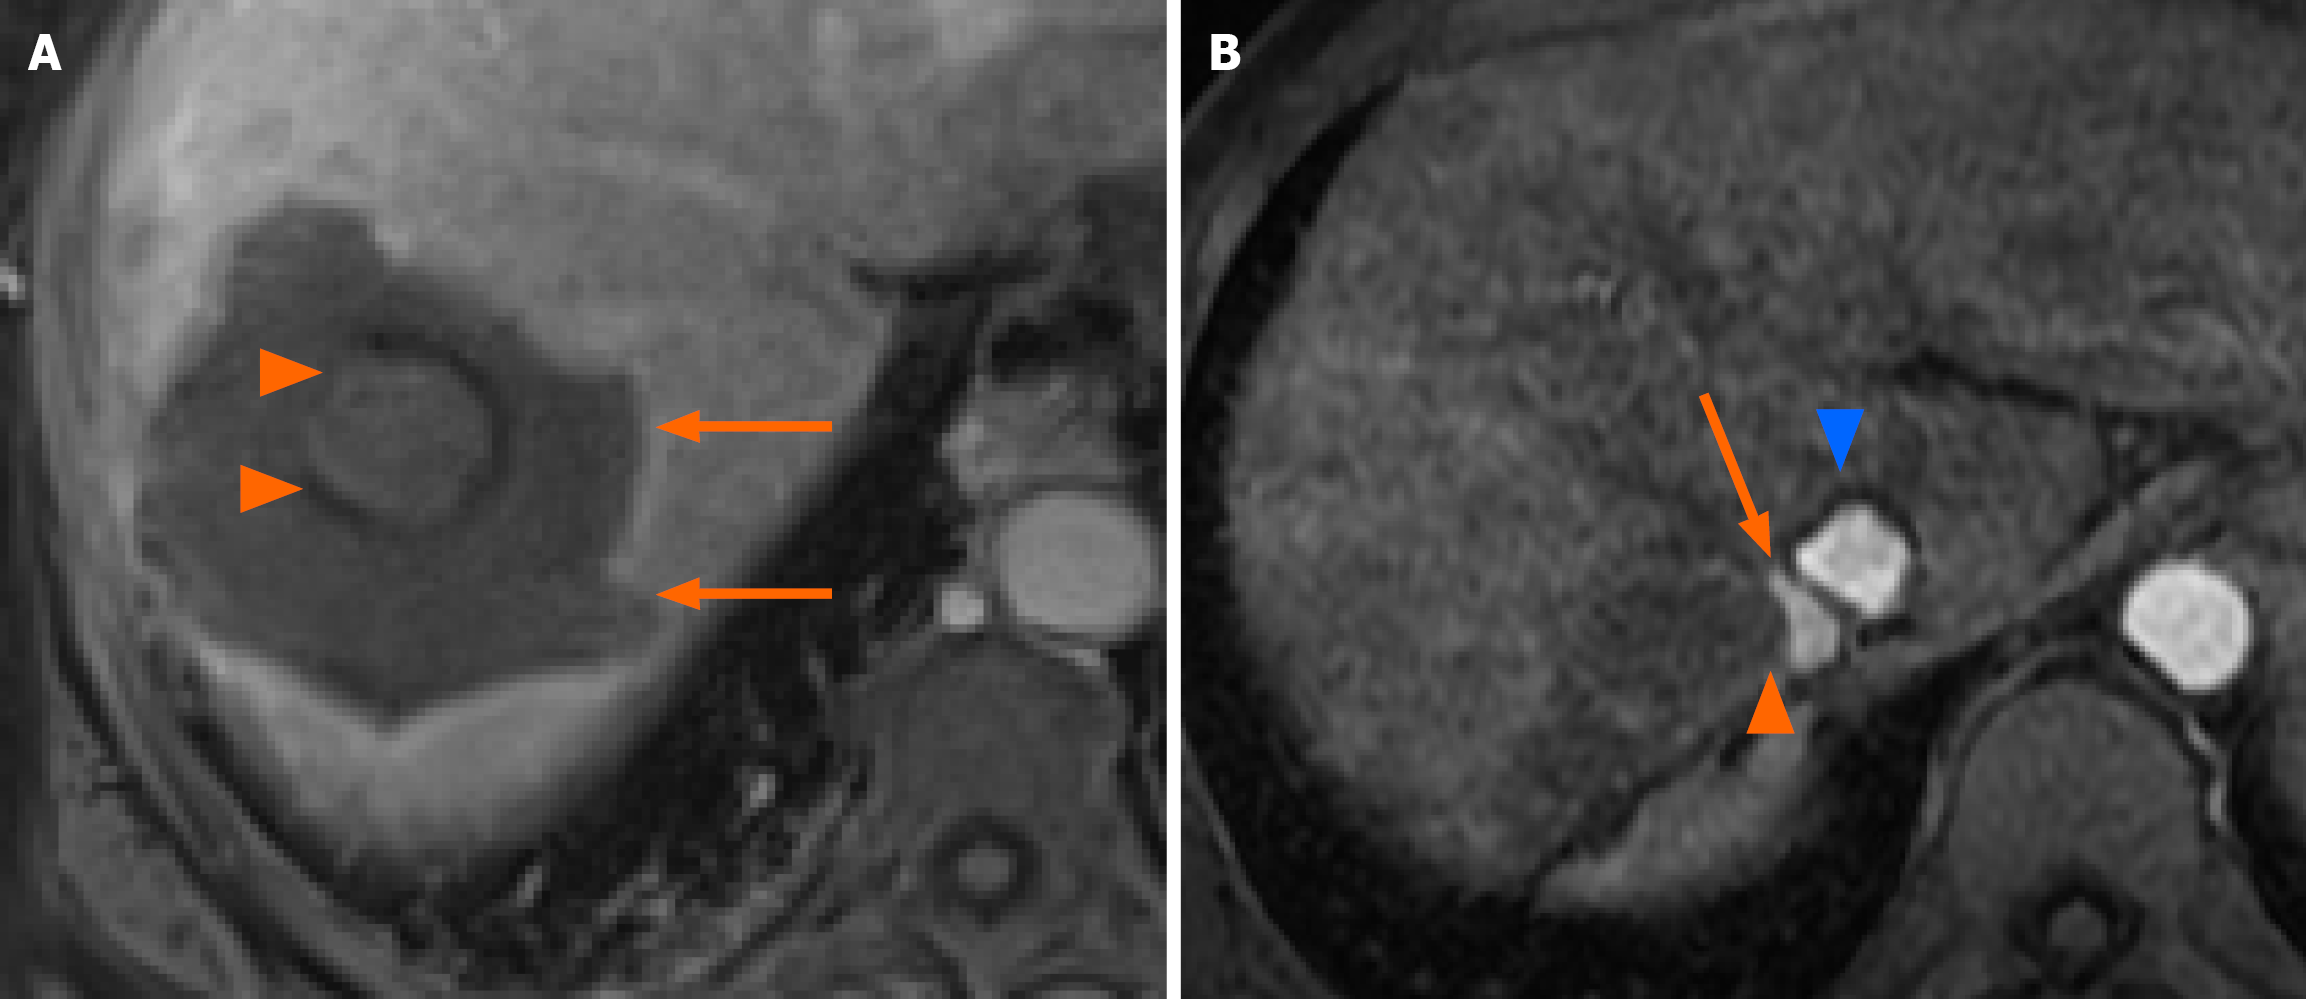

Figure 2 Representative depictions of ablation margins and local tumor progression after thermoablation on magnetic resonance imaging.

A: A portal phase magnetic resonance imaging performed one month post multibipolar radiofrequency ablation showing optimal (> 5 mm) ablation margins between the original lesion (arrowheads) and the ablation zone (arrows); B: An arterial phase magnetic resonance imaging showing the appearance of a local tumor progression (arrow) after microwave ablation occurring between the ablation zone (arrowhead) and the inferior vena cava (blue arrowhead).